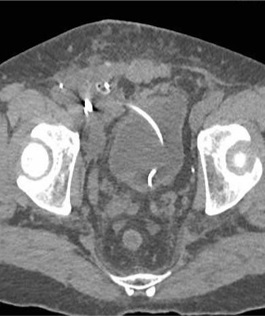

淋巴造影影像

淋巴造影8天后淋巴漏确定改善

肾移植术后淋巴漏